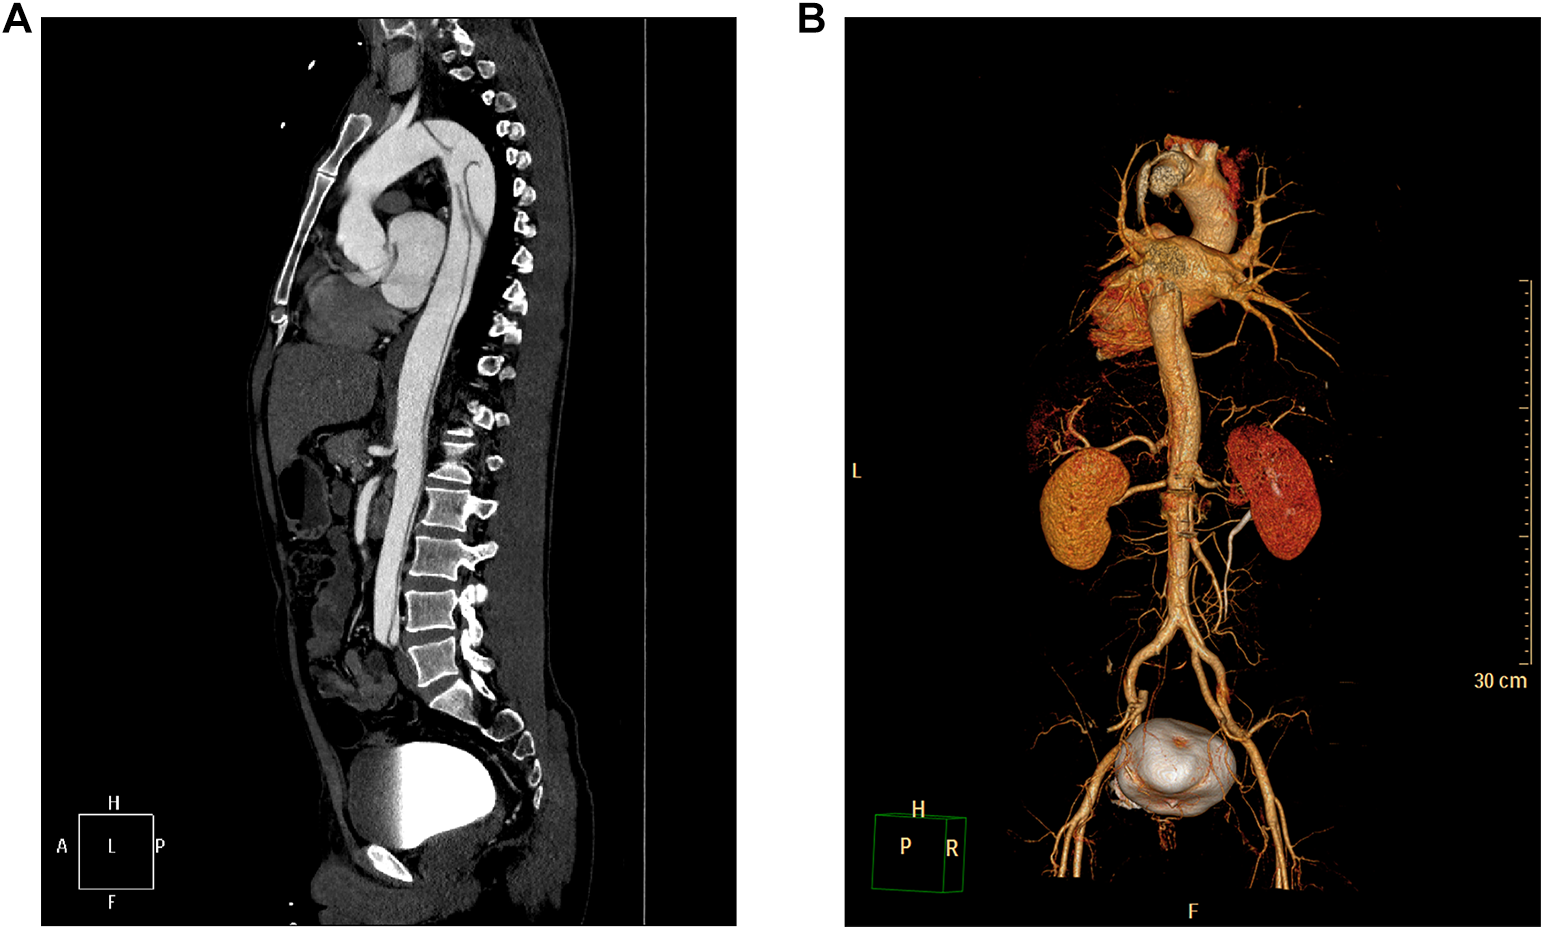

Figure 3

CTA showing medial migration of the intimal sheet from the descending thoracic aorta to the level of both common iliac arteries, and the lumen showing “double-lumen” changes, consistent with aortic dissecting aneurysms (Stanford type B). (A) Maximal intensity projection of the sagittal section of the aorta. (B) Three-dimensional reconstruction of the aorta.

Physical examination revealed an acutely ill face, clear consciousness, poor spirit, heart rate of 125 beats/min, blood pressure of 210/94 mmHg, distended abdomen, drum sounds on percussion, no tenderness or rebound tenderness, and the presence of femoral and dorsalis pedis pulses. According to the aortic dissection detection risk scoring (ADD-RS) system proposed by the aortic diagnosis and treatment guidelines in 2014, ADD-RS = 1. The etiology of the patient was unknown; clinicians could not rule out aortic dissection, urinary calculi, or other related diseases; therefore, echocardiography and abdominal urinary ultrasonography were performed on the patient. Echocardiography showed normal findings, and abdominal ultrasonography revealed a mass in the left adrenal region (72 × 57 mm, Figure 1). Contrast-enhanced computerized tomography (CT) of the abdomen revealed that the intimal flap moved inward from the descending part of the thoracic aorta to the level of the bilateral common iliac arteries, the lumen showed “double-lumen” changes, the right renal artery opened into the false lumen, and the left renal artery opened into the true lumen, consistent with aortic dissecting aneurysm (Stanford type B). A soft tissue mass was observed in the left adrenal gland, with uneven density, approximately 61 × 53 mm in size, with a clear boundary, and with significant enhancement after contrast-enhanced scanning in which there was necrosis; pheochromocytoma was first considered (Figure 2). The patient subsequently underwent aortic computed tomographic angiography (CTA), which revealed Stanford TBAD (Figure 3). Laboratory tests showed a 24-h urine vanillylmandelic acid (VMA) level of 20.51 mg/24 h (reference value: ≤12 mg/24 h) and a D-dimer level of 6.75 mg/L (reference range 0.0–0.5 mg/L).